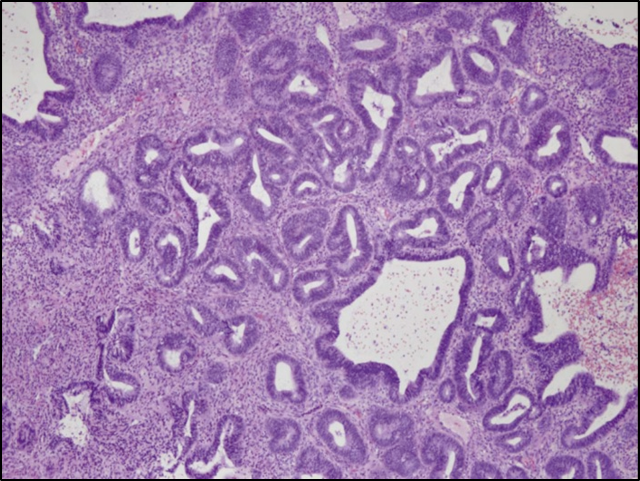

Identify ?

Graves disease-

Autoimmune condition.

Microscopy-

Papillary projection & columnar epithelial lining with scaloping edges.